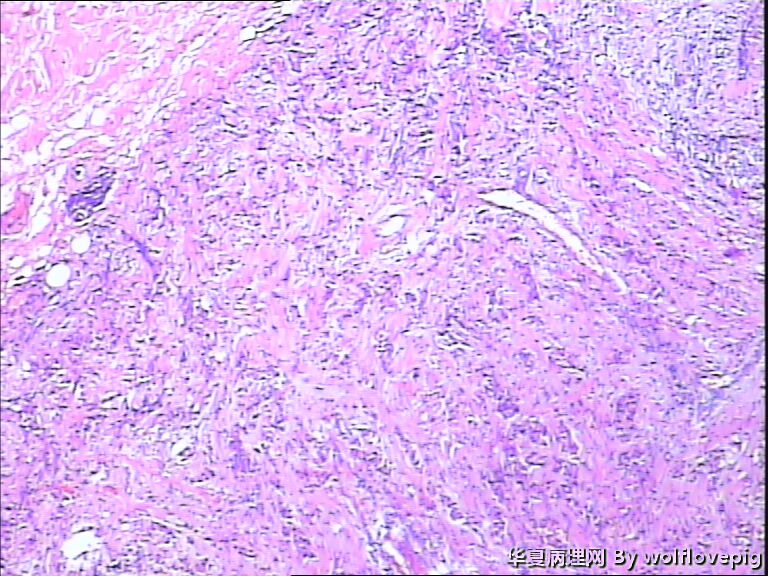

女,60y,发现右乳包块6+月。

灰白不整形组织一块:3*2*1.5cm,切面有一灰白区域,边界欠清,质韧。

图1